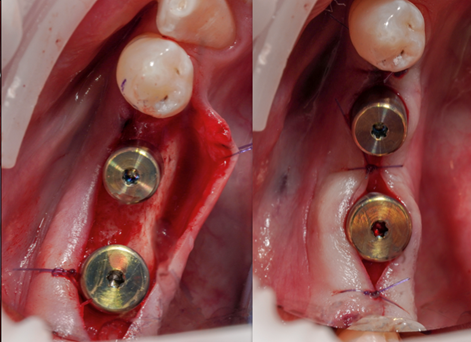

• Živý zákrok na pacientovi

• 13:00 – 14:30 LIVE zákrok soloimplantace na pacientovi.

• 14:30 – 15:00 Hands on